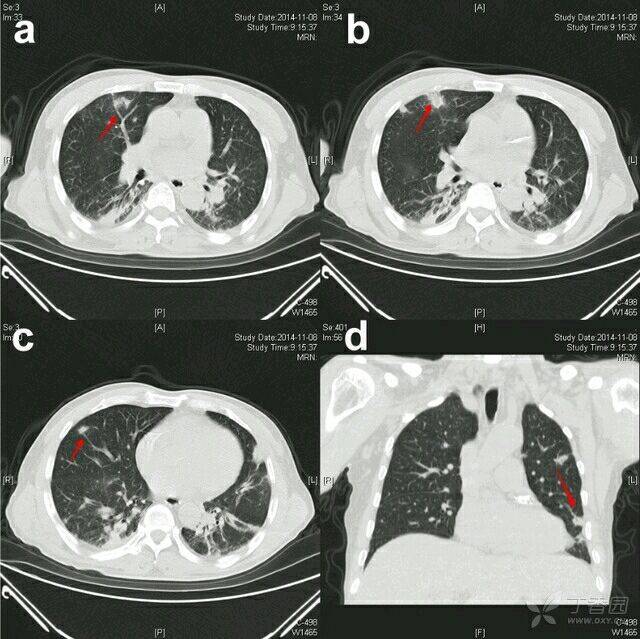

男性患者,于两周前无明显诱因下出现发热,体温最高时 40 ℃,伴畏寒,咳嗽,咳少量黄白色痰。当地医院血培养示金黄色葡萄球菌,对苯唑西林、利奈唑胺、万古霉素均敏感,给予抗感染治疗(具体用药不详),仍持续发热,出现全身多发皮疹及水泡。遂入院。 胸部 CT(图 1 a ~ d)示双肺周边大小不一的多发斑片、结节及条索影,部分结节可见空洞、滋养血管征,行血培养示金黄色葡萄球菌,诊断为「肺炎,金黄色葡萄球菌败血症」,给予利奈唑胺静脉滴注,皮肤水泡消退,仍发热。 图 1 a. 胸部 CT 示可见滋养血管征连接(箭头示);b. 右肺中叶可见较大结节(箭头示),双下肺可见斑片、条索影;c. 右肺中下叶多个小结节,部分结节可见滋养血管征(箭头示);d. 左肺可见胸膜下楔形影,见滋养血管征(箭头示) 两天后胸部 CT(图 2)示双肺斑片、结节影,较前部分增大,部分缩小,双肺下叶部分实变,双侧胸腔积液,给予静脉滴注万古霉素,效果不佳。 图 2 胸部 CT 示双肺周边新发结节影,大小不等,部分可见滋养血管征(箭头示)。双侧胸腔积液,双肺下叶部分肺组织实变 检查结果 体温 38.3 ℃,脉率 102 次/min,呼吸频率 26 次/min,血压 140/79 mmHg,体质虚弱,全身皮肤凹陷性水肿,右前臂皮肤可见直径约 2 cm 红肿破溃,左前臂可见直径约 6 cm 皮肤瘀斑,臀部散在皮肤破溃结痂。全身浅表淋巴结无肿大。双肺呼吸音粗,可闻及湿啰音。双下肢肌肉萎缩,肌力 4 级。 血常规示白细胞为 11.53×109/L,血小板为 67×109/L;D - 二聚体 2940 mg/L;血生化检测示总蛋白 46 g/L,白蛋白 20 g/L,肝肾功正常;血气分析(吸空气)示 pH 为 7.56,PaO2 为 67 mmHg,PaCO2 为 30 mmHg,SaO2 为 95% 。入院初步诊断:脓毒症,金黄色葡萄球菌肺炎。 治疗经过 入院后给予万古霉素、头孢哌酮舒巴坦,输注白蛋白、血小板、控制血糖等治疗。血气分析(吸氧 2 L/min)pH 为 7.52,PaO2 为 161 mmHg,PaCO2 为 29 mmHg,SaO2 为 98%;2 次血培养(发热时抽取)为金黄色葡萄球菌;1 次尿培养示近假丝酵母菌。2 次痰培养示鲍氏不动杆菌(++,B 级);降钙素原为 0.748 µg/L。 心脏超声:肺动脉高压(轻 - 中度)。复查血常规示白细胞为 7.25×109/L,血小板为 121×109/L,D-二聚体 > 1050 µg/L。患者仍间断发热,最高体温在 38 ℃ 左右。 入院后 7 日后胸部 CT(图 3)示双肺阴影未见吸收,胸腔积液较前增多。B 超见左臂多处软组织脓肿,右上肢、双下肢及臀部炎性包块超声表现。换用替考拉宁、哌拉西林舒巴坦抗感染,并双侧胸腔微创置管,引流液呈淡黄色,胸腔积液培养阴性,胸腔积液常规示漏出液。 图 3 胸部 CT 示右肺斑片结节影(箭头示)较图 1 b 和图 2 增大,双侧胸腔积液较图 2 增多 入院 18 日后胸部 CT(图 4)可见双肺多发性斑片、结节影部分吸收,胸腔积液减少。并行左臂多处脓肿切开引流,脓液呈暗红色脓血样,培养示金黄色葡萄球菌,每日清洁换药。右股后脓肿行穿刺置管引流。 图 4 胸部 CT 示双肺斑片结节影(箭头示)较前不同程度吸收。胸腔积液较前减少,右侧为著 入院 36 日胸部 CT(图 5)双肺多发斑片、结节影大部分吸收,胸腔积液减少。患者体温恢复正常,予拔除胸腔微创置管。予抗生素降阶梯治疗:静脉滴注头孢曲松、盐酸莫西沙星。复查血、尿、痰培养均阴性, 其余指标逐渐恢复正常。患者轻微咳嗽,无其他不适,好转出院。 图 5 胸部 CT 示双肺周边多发性斑片、结节、楔形影大部分吸收,双侧胸腔积液减少 最后诊断:脓毒症,脓毒性肺栓塞,多发软组织脓肿。